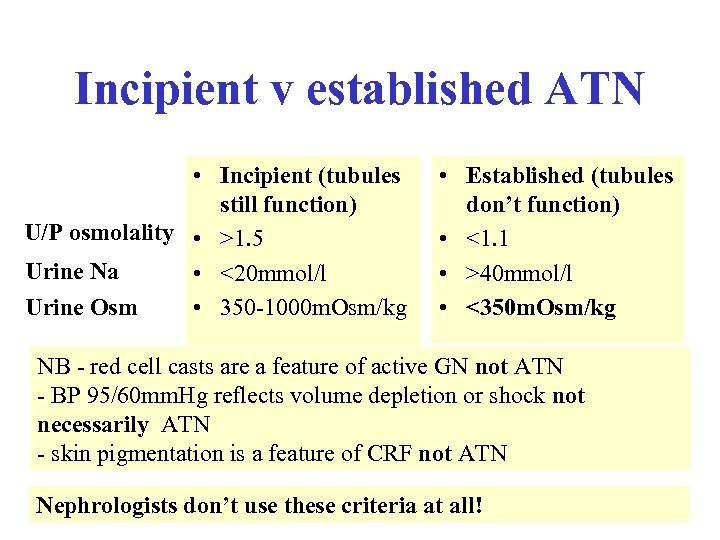

5 A 62 -year-old man develops oliguria 48 hours after a laparotomy for bowel obstruction. Which of the following would be most suggestive of acute tubular necrosis rather than pre-renal uraemia • • A Urinary sodium less than 10 mmol/L B Blood pressure 95/60 C Red cell casts D Urinary osmolality of less than 350 mosm/Kg • E Increased skin pigmentation

5 A 62 -year-old man develops oliguria 48 hours after a laparotomy for bowel obstruction. Which of the following would be most suggestive of acute tubular necrosis rather than pre-renal uraemia • • A Urinary sodium less than 10 mmol/L B Blood pressure 95/60 C Red cell casts D Urinary osmolality of less than 350 mosm/Kg • E Increased skin pigmentation

5 A 62 -year-old man develops oliguria 48 hours after a laparotomy for bowel obstruction. Which of the following would be most suggestive of acute tubular necrosis rather than pre-renal uraemia • • A Urinary sodium less than 10 mmol/L B Blood pressure 95/60 C Red cell casts D Urinary osmolality of less than 350 mosm/Kg • E Increased skin pigmentation

5 A 62 -year-old man develops oliguria 48 hours after a laparotomy for bowel obstruction. Which of the following would be most suggestive of acute tubular necrosis rather than pre-renal uraemia • • A Urinary sodium less than 10 mmol/L B Blood pressure 95/60 C Red cell casts D Urinary osmolality of less than 350 mosm/Kg • E Increased skin pigmentation

Incipient v established ATN • Incipient (tubules still function) U/P osmolality • >1. 5 Urine Na • <20 mmol/l Urine Osm • 350 -1000 m. Osm/kg • Established (tubules don’t function) • <1. 1 • >40 mmol/l • <350 m. Osm/kg NB - red cell casts are a feature of active GN not ATN - BP 95/60 mm. Hg reflects volume depletion or shock not necessarily ATN - skin pigmentation is a feature of CRF not ATN Nephrologists don’t use these criteria at all!

Incipient v established ATN • Incipient (tubules still function) U/P osmolality • >1. 5 Urine Na • <20 mmol/l Urine Osm • 350 -1000 m. Osm/kg • Established (tubules don’t function) • <1. 1 • >40 mmol/l • <350 m. Osm/kg NB - red cell casts are a feature of active GN not ATN - BP 95/60 mm. Hg reflects volume depletion or shock not necessarily ATN - skin pigmentation is a feature of CRF not ATN Nephrologists don’t use these criteria at all!